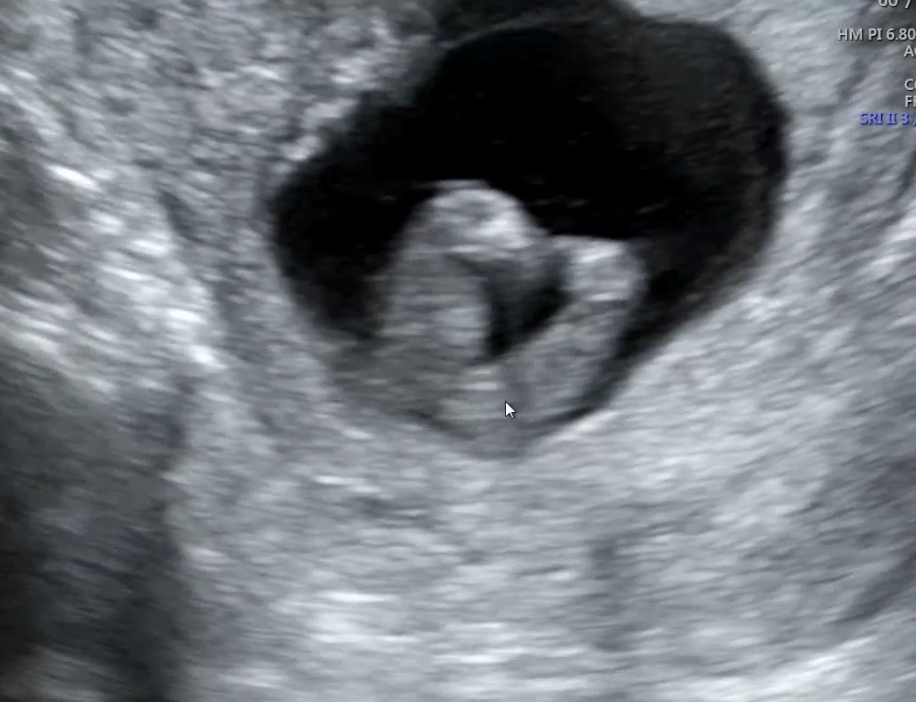

다리사이에 아무고토 없는걸까요?!

다리로 핫트핫트 만들고 있는 녀석 곧휴는 안보이는거 같은데... 14주입니다🥹

ㅠ딸은 20주까지 방심 금물이요 매끈한거보고 딸 확정받은 분 중에 다음 진료때 숨겨있던 꼬추보였다고하더라구요

우왓 딸이군여! 아들은 저자세에 삼각점 존재감 장난아니거든요!!

다리 하트 너무 귀여워요 .. 딸이신것같아요!! 저는 13주차에 다리사이로 뭐가 선명하게 띠용 보였거둔요. 움직임도 활발하고 다들 주변에 물어보니 아들이라고 얘기하던데... 선생님이 정확히는 말씀안해주셨는데 뉘앙스가 저는 아들램 같아요..! 작성자님은 다리가 매끈한게 딸램인 것 같아요.